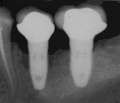

Область с единственным отсутствующим зубом

Через десну делается разрез, и лоскут ткани откидывается, чтобы показать кость челюсти.

Как только кость обнажена, серия упражнений создаёт и постепенно увеличивает участок (называемый остеотомией) для установки имплантата.

Крепление имплантата превращается в остеотомию. В идеале он полностью покрыт костью и не имеет движения внутри кости.

Формирователь десны (опора для заживления) прикрепляется к креплению имплантата, а лоскут десны накладывается на заживляющий абатмент.